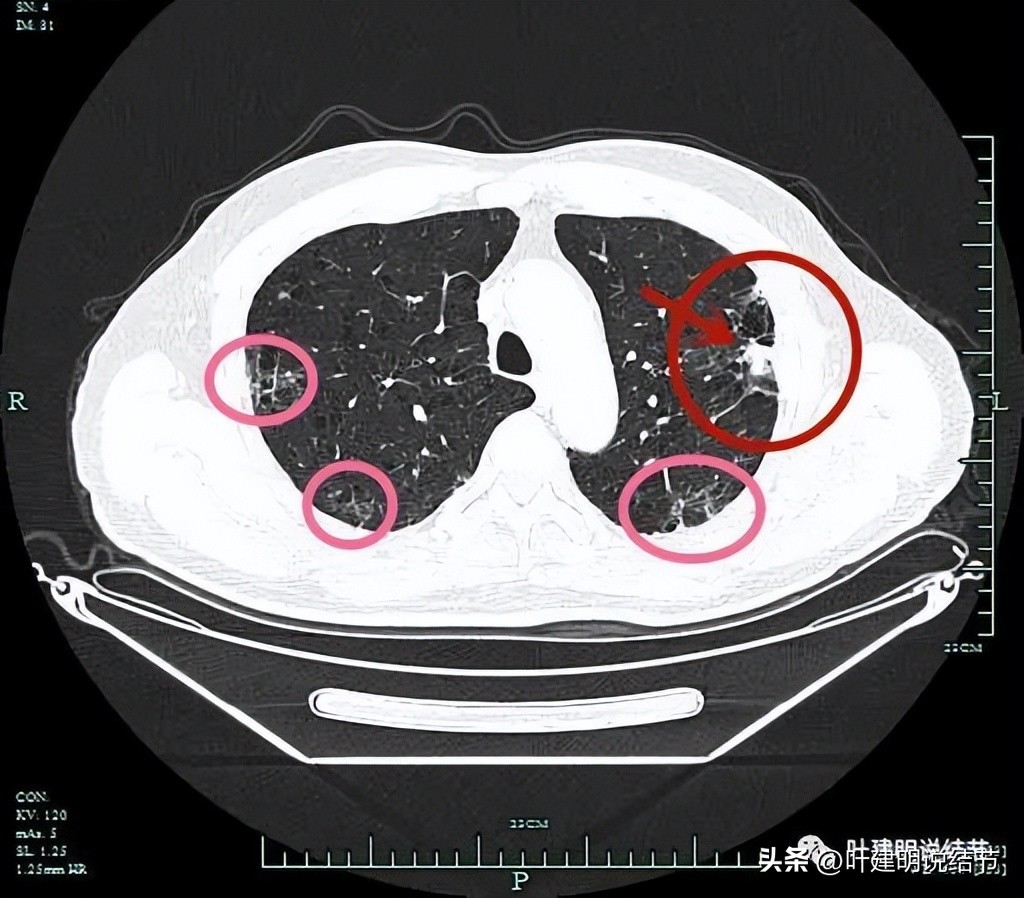

病灶实性,边上条索状并有局灶肺气肿的样子(纹理稀疏)。

病灶实性,有一定膨胀性,表面不平滑。

局部有细毛刺(紫色箭头)。